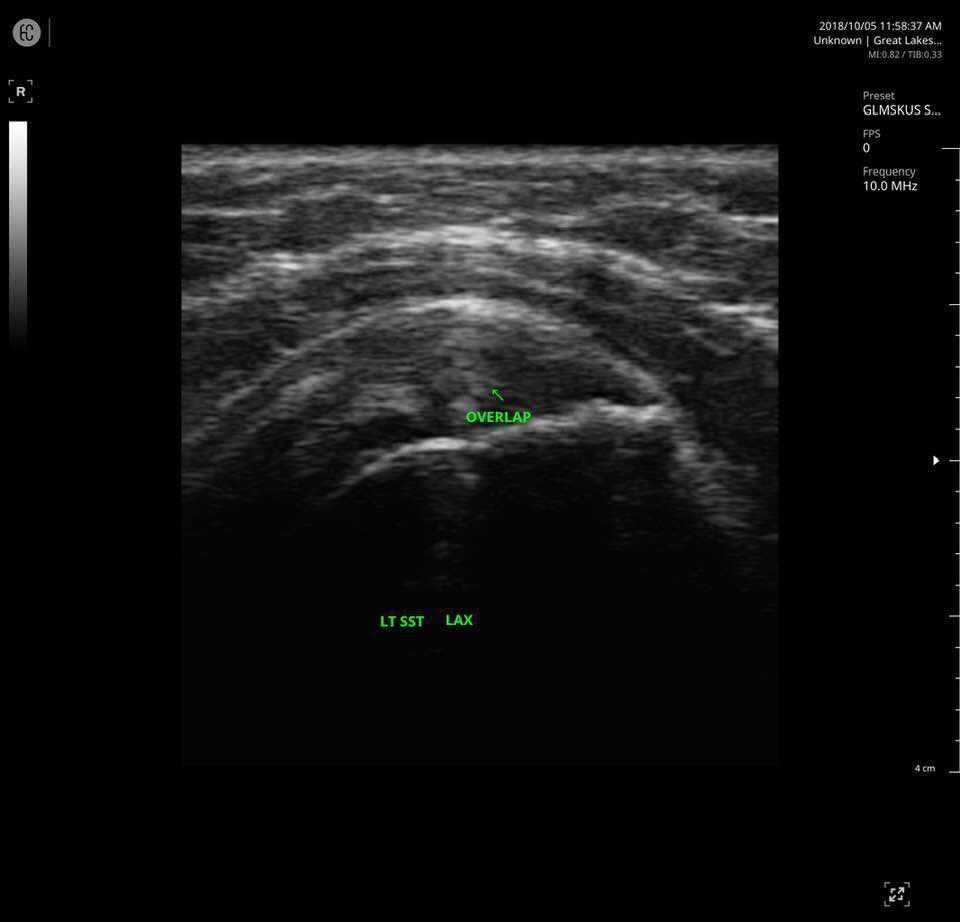

The SONON 300L transducer has cutting-edge technology and its software, combined with a proprietary sensor, turns any mobile device into a mobile ultrasound monitor with the same image quality and knobology as a traditional US machine. Software includes individual preset settings for your most common test.

- MSK

Specifications for SONON 300L:

- Multi-frequency: 5MHz 7.5MHz 10MHz

- Depth: max 10cm

- Field of View: 40mm